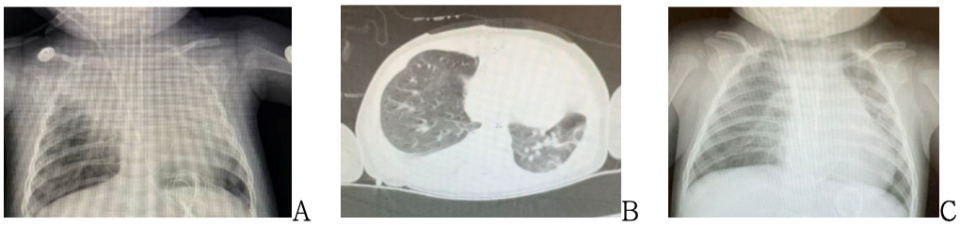

A:10.28胸片; B: 10.28胸部CT;   C:11.2胸片

2025.10.25胸片:心脏术后,两肺纹理增多增粗,右肺尖斑片状高密度影,肺实变或肺不张可能,较前2025-10-24新增,右侧胸腔少许积液。

10.28胸片:心脏术后,右上肺及左肺散在斑片状高密度影,肺实变考虑,较前2025-10-27进展,左侧胸腔少量积液。

10.28肺部CT:支气管炎伴两肺多发感染,伴部分肺实变、不张,两侧胸腔积液,伴右下肺部分膨胀不全;

11.2胸片:心脏术后,两肺渗出性改变,对比2025-10-31老片有所吸收。